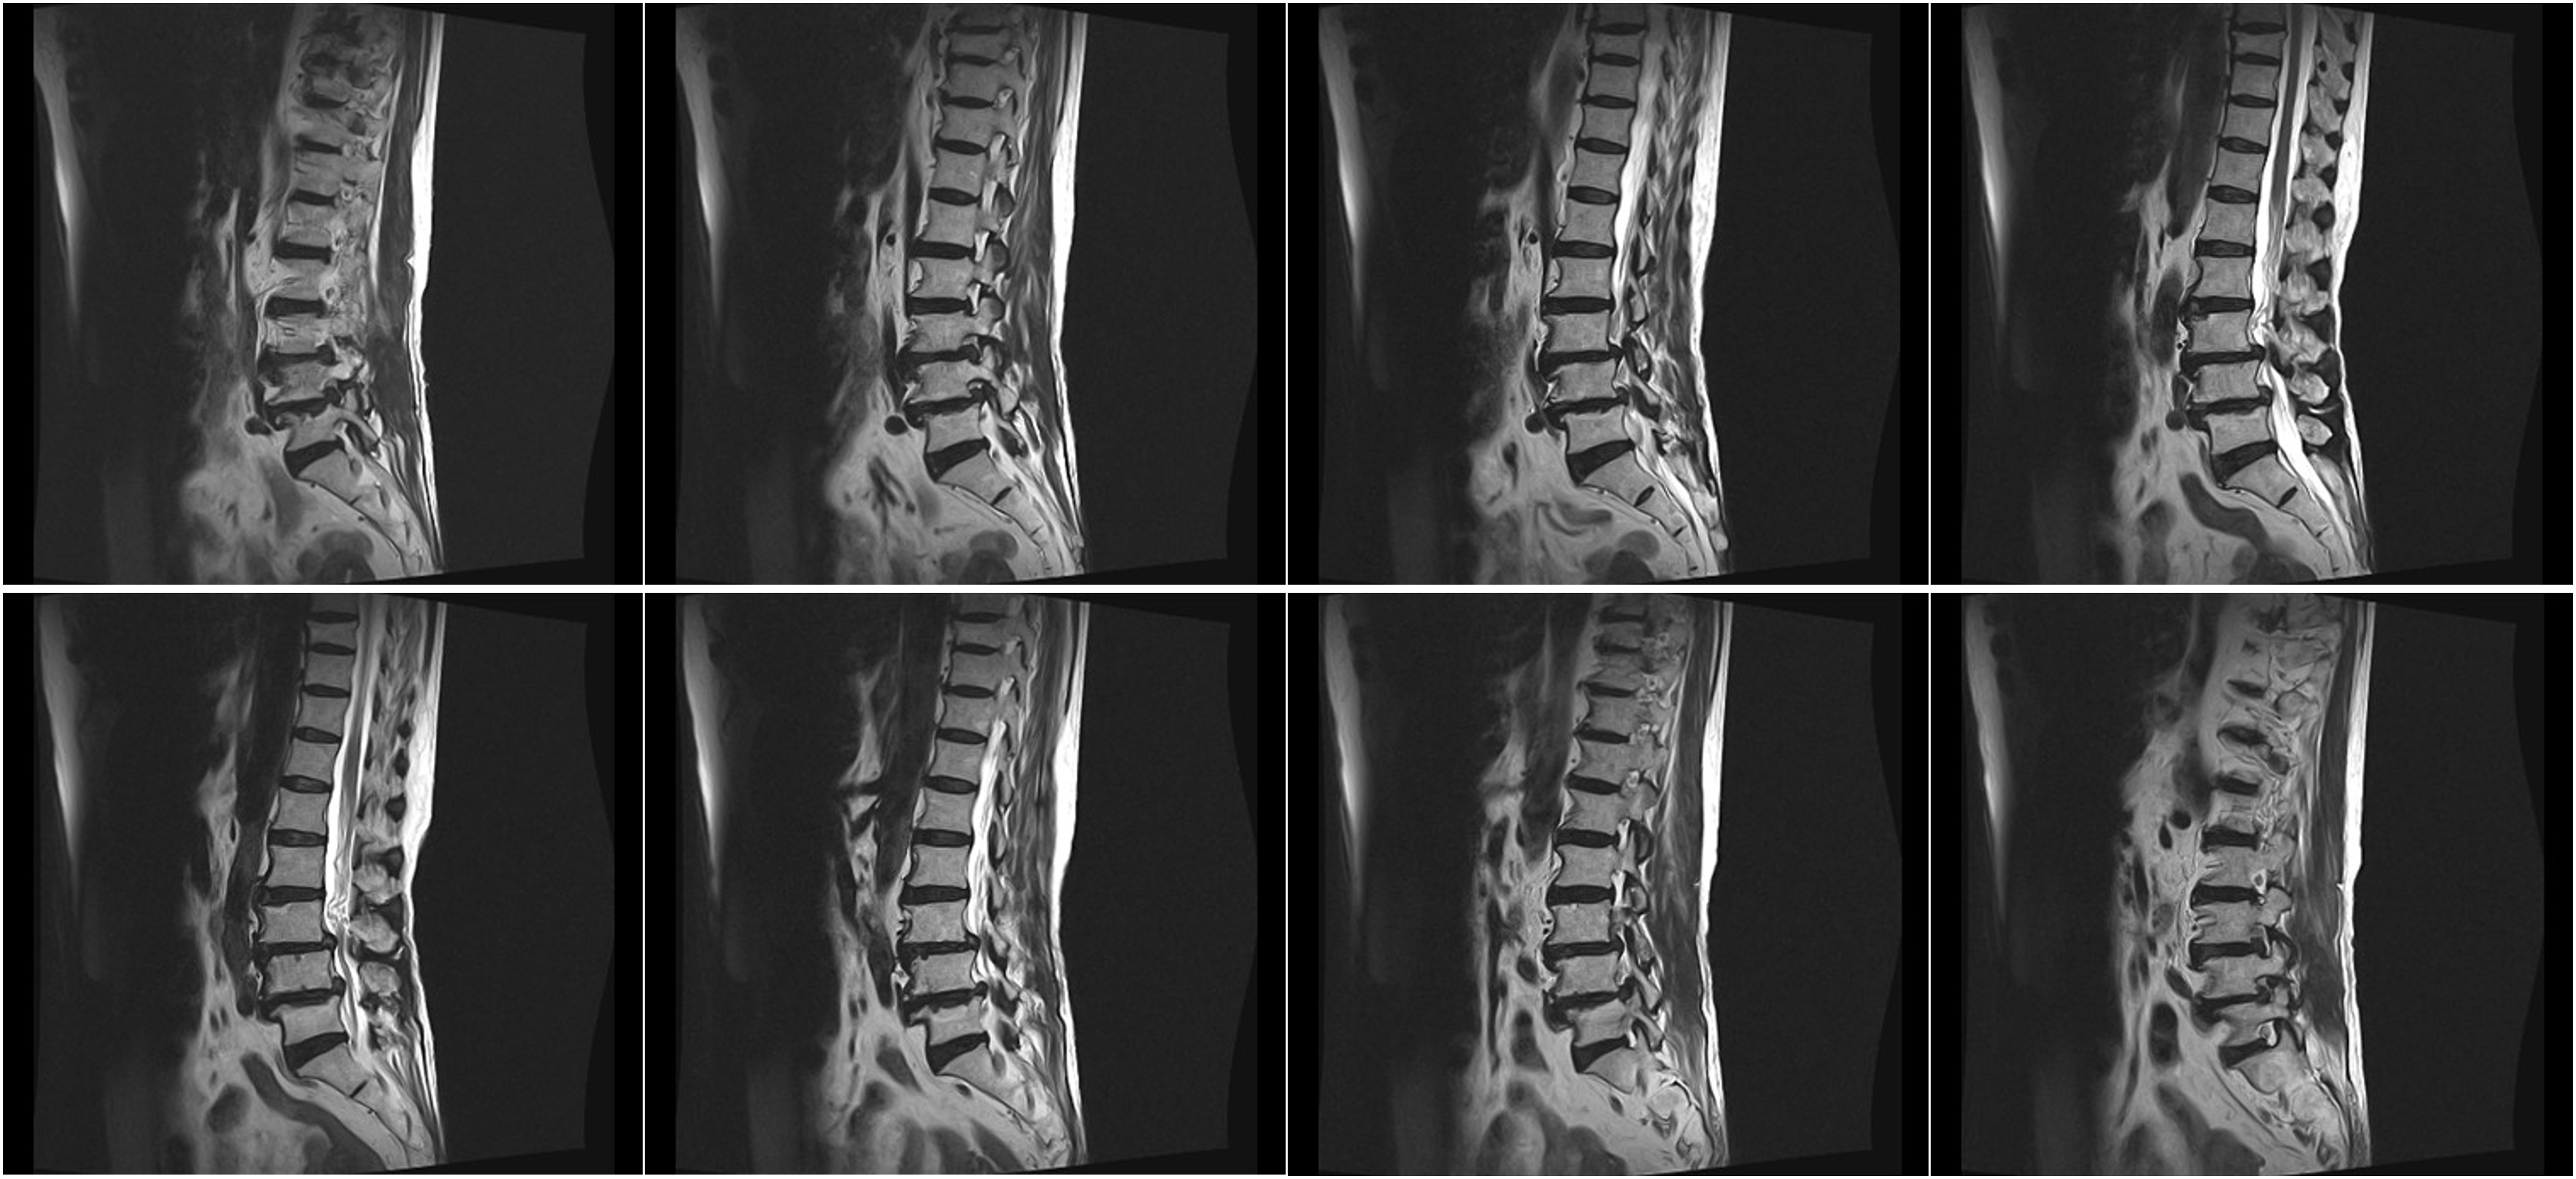

Hình ảnh lâm sàng